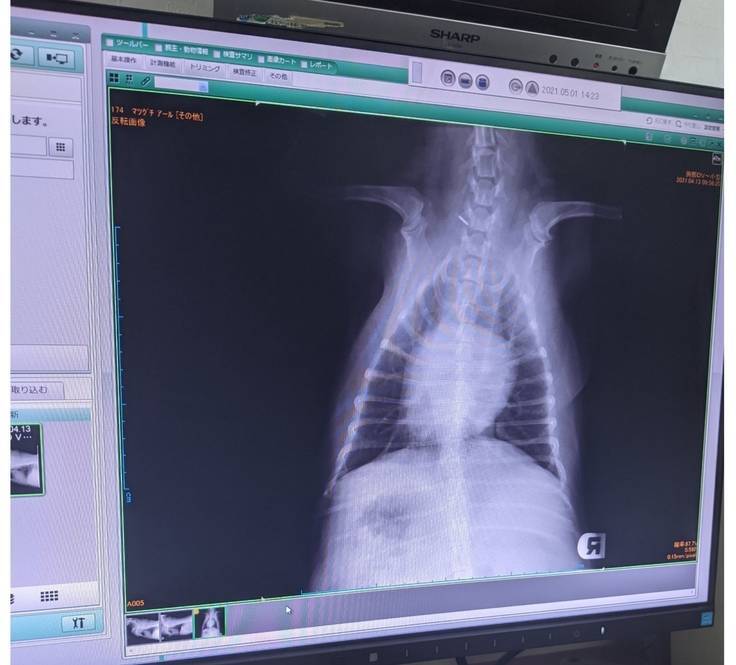

診断書

去年10月末、2月中旬、4月は2回、動物病院で診察を行って頂き検査で重度レベル4気管の75%以上虚脱状態とわかりました。

※診断書椎間板ヘルニア